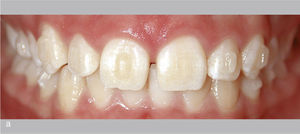

La expansión transversal constituye una alternativa a la reducción de esmalte interproximal para corregir apiñamientos y para dotar a las arcadas de un aspecto armonioso. La figura 4a muestra un maxilar estrecho en el plano transversal y dientes muy rotados y apiñados en el sector anterior. En este caso fue posible lograr una arcada armoniosa utilizando anclajes en los dientes 14, 13, 23 y 24 con ataches verticales, expansión transversal, protrusión del diente 21 y reducción del esmalte interproximal (fig. 4b).

Sector anterosuperior con dientes 11 y 21 en mesioversión y triángulo negro interdental (a). Se colocaron ataches rectangulares verticales en los dientes 11 y 21 y en los anteriores adyacentes. Resultado del tratamiento después de enderezar los dientes 11 y 21 y de cerrar el triángulo negro (b).